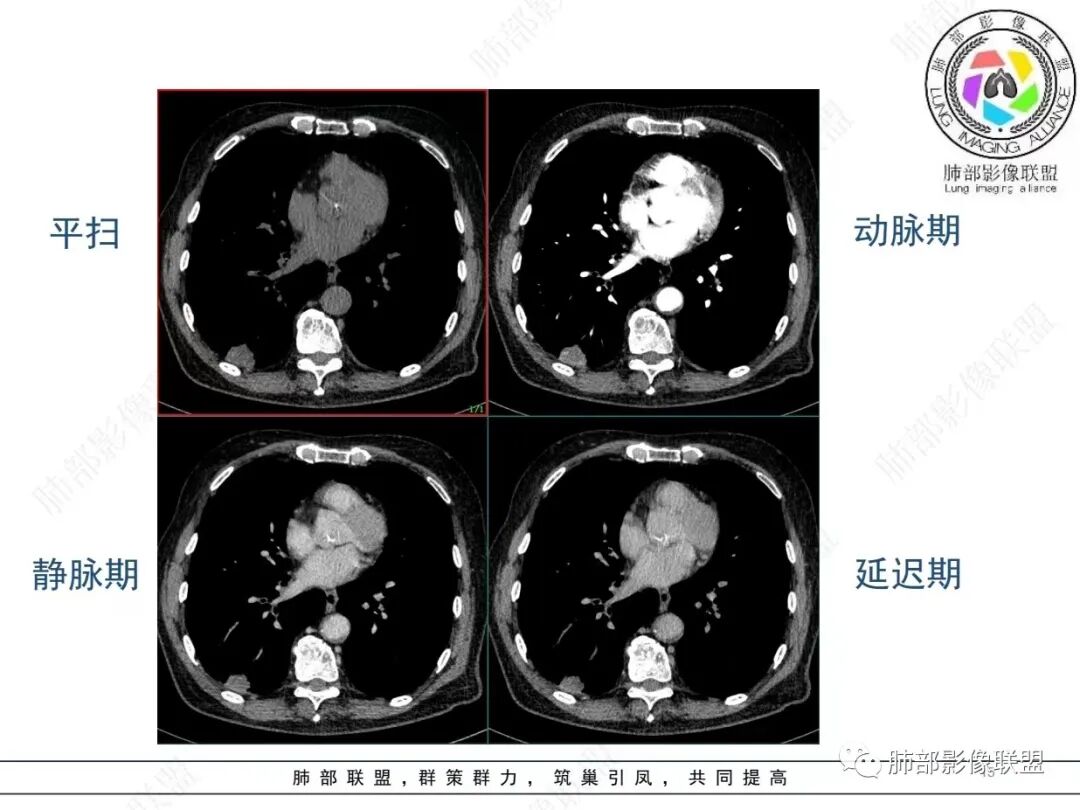

老年男性,发作性气喘,实验室检查白细胞增高。肺部影像表现:右肺胸膜下占位性病变,肺气肿背景,内部可见空腔/空泡影,周围可见小结节,增强动脉期明显强化,静脉期及延迟期强化减低,右侧肺门可见肿大淋巴结,有吸烟史,近年减少,首先考虑恶性肿瘤,肺小细胞癌/鳞癌,隐球菌作为鉴别诊断,病例穿刺活检。

老年男性,气短,胸痛半年,考虑慢性病史,无发热,常见的肺部感染可以排除,右肺下叶基地段靠近胸膜实变影,边缘清楚,不均匀强化,可见空泡征,点状血管影,周围小叶中央型结节,有网格影,支气管扩张,磨玻璃影,肺间质改变,右侧肺门淋巴结肿大,综合考虑恶性肿瘤并肺内转移

老年男性,胸疼入院,影像表现,右肺下叶胸膜下结节,边界清晰,与支气管关系不密切,病灶内见空洞?增强病灶均匀强化,右肺门可见增大淋巴结,考虑恶性病变,小细胞癌,其次鳞癌

老年男性,肺气肿背景,右肺下叶,右肺下叶胸膜处实性结节,形似山丘,有分叶,病灶内可见扩张细支气管/空泡,边缘可见弯曲血管,增强后不均匀强化,可见血管影,病灶胸膜侧呈小波浪??状,局部突入胸膜面,右肺门肿大淋巴结。考虑恶性结节,小细胞肺癌,腺癌,鉴别炎性肉芽肿。建议ct下穿刺活检。

老年男性,肺气肿病史,支气管束增粗,管壁增厚,右肺下叶后基底段胸膜下肿块,土豆征,边界清,有膨隆,小支气管边缘阻断,见集血管束征,肿块强化明显(快进快出特点),并偏心空洞,胸膜下栽赃,周围肺结构破坏(蜂窝状影表现),右肺门淋巴结转移肿大,血管内皮生长因子偏高,肿块与小支气管,血管束关系密切,强化特点,定恶性肺肿瘤,小细胞Ca。

老年男性,肺气肿,右肺下叶胸膜下结节,边缘毛躁,周围多发间质增厚,临近胸膜下脂肪间隙模糊,增强后动脉期不均匀强化,延迟期强化较低,右肺门肿大淋巴结,考虑恶性,鳞癌,小细胞肺癌,鉴别炎性肉芽肿性结节

右肺下叶胸膜下结节,边界清,边缘平直膨隆,血管集束,其内空洞,明显不均匀强化,考虑腺癌?小细胞癌?鉴别隐球菌

肺气肿,胸膜下结节,边界清晰,边缘毛糙,病灶内见空洞,增强病灶均匀强化,右肺门可见增大淋巴结,考虑恶性病变,小细胞癌,其次鳞癌,鉴别隐球

老年男性,肺气肿背景,右肺下叶胸膜下团块影,明显强化,其内空泡征,周边血管聚集,右肺门淋巴结增大,考虑腺癌?

右下叶胸膜下结节,宽基底与胸膜相连,结节与胸膜相交呈钝角〈山丘征〉,内可见充气扩张的支气管,中度强化,结节边缘无毛刺,内见走行自然的血管影,提示破坏力及收缩力差,右肺门可见肿大淋巴结,老年烟民,考虑恶性占位,支持小细胞癌

右肺下叶胸膜下结节,呈山丘状,生长在慢支肺气肿间质纤维化的基础上,边缘相对光滑清晰,右肺门淋巴结肿大,强化呈速升速降,老年男性,吸烟史,考虑小细胞肺癌,鉴别隐球

老年男性,吸烟史40年,肺气肿背景,胸膜下结节,边缘膨隆,增强后结节内有片状坏死区,右肺门及纵隔肿大淋巴结,考虑恶性,鳞癌?小细胞代排

老年患者,右下肺胸膜下结节,有血管聚集、空泡征,强化明显,右肺门见肿大淋巴结。考虑腺癌,鉴别肉芽肿性病变

老年男性,长期抽烟病史,右下肺胸膜下结节,有分叶,胸膜下栽桩,肿块增强可见明显不均匀强化,考虑恶性,鳞癌可能性大,鉴别小细胞肺癌。

恶性明确(右肺门淋巴结明显肿大,中心坏死,坏死边界不清楚,胸膜下馒头样肿块,血管集束,支气管阻塞,动脉期明显强化,内部明确的供血血管提示肿瘤细胞密集,局部坏死边界不清,强化快进快出,邻近胸膜强化呈胸膜尾征,提示胸膜受侵),病理符合周围性低分化鳞癌(老年男性,长期吸烟史,肿块强化明显,快进快出,坏死边界不清楚,阻塞性炎症及阻塞性肺气肿,肺门淋巴结肿大,坏死,邻近支气管壁增厚支持粘膜下侵润生长),白细胞总数高,动脉期强化那么明显,腺癌合并感染倒是要高度警惕。

老年男性,吸烟史+肺气肿背景,右下肺胸膜下肿块(坏死+内部血管影+快进快出),右侧肺门淋巴结肿大,考虑:恶性、鳞?高级别腺待排(总体感觉偏软)。

男,80,发作性气喘半年,加重1天。长年大量吸烟史。肺部CT:肺气肿背景,右肺胸膜下实性占位,处于外周大疱带与气肿带交界,山丘征,边缘膨隆,边界较清,血管集束,周围可见小结节。增强不均匀强化,内可见迂曲模糊血管影,右肺门、隆突下可见肿大淋巴结。首先考虑恶性肿瘤,小?鳞?鉴别PC、TB等。